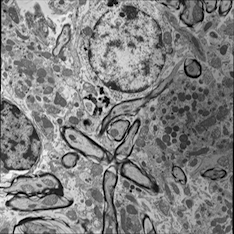

For image analogies based image registration, I have corresponding TEM/Confocal Microscopic image pairs of mouse brains with corresponding regions highlighted by a box. Using the correlative microscopy technique on the mouse brain, I want to localize specific brain regions associated with Pelizaeus-Merzbacher Disease (PMD) and do quantitative assessment of hypomyelination and demyelination in mice. PMD is one of a group of genetic disorders characterized by progressive degeneration of the white matter of the brain affecting the myelin sheath, the fatty covering that acts as an insulator on nerve fibers in the central nervous system.

The confocal microscopy images are multichannel color images in our test dataset. The blue channel is based on the blue stain DAPI (a fluorescent stain) which stains the DNA of the cell nucleus and corresponds to dark regions within the nuclei in the TEM. The green channel is based on the stains of the myelin sheats, visible as dark black layers covering the neurons in the TEM images. The red channel is not explicitly stained for and is caused by the auto-fluorescent effect of lipofuscin. The confocal image with RGB channels and its corresponding TEM image are shown in Fig. 5.

Currently I have six pairs of 2D TEM/confocal images with resolutions 582.24 pixels per μm𝜇𝑚\mu m and 7.5887.5887.588 pixels per μm𝜇𝑚\mu m respectively (1μm=1micron=106m1𝜇𝑚1𝑚𝑖𝑐𝑟𝑜𝑛superscript106𝑚1\,\mu m=1\,micron=10^{-6}\,m). The resolution is different between two images and only a small region in the confocal image corresponds to the TEM image.

5.3 Image Analogies based Image Registration

5.3.1 Pre-processing

In the pre-processing step, I extract the corresponding region of the confocal image and resample both confocal and TEM images to an intermediate resolution. The final resolution is 14.52 pixels per μm𝜇𝑚\mu m, and the image size is about 200×200200200200\times 200 pixels, which is dependent on the original TEM image size.

From the example in Fig. 5, the blue and red channels are too noisy and contain less information compared to the green channel. We use only the green channel as grayscale image for the registration in our application. The datasets are roughly registered based on manually labeled landmarks with a similarity transformation model.

Refer to caption

(a) Red channel of confocal image

(b) Green channel of confocal image

(c) Blue channel of confocal image

(d) Grayscale of confocal image

(e) Confocal image

(f) TEM image

Figure 5: Example of Confocal image with RGB channels and TEM image